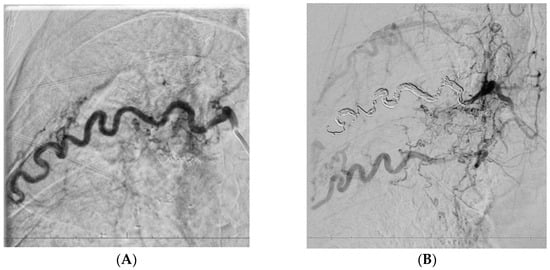

| P06 | Consolidation in S6 of LLL Fibrotic right lung with basal fibrosis | LIMA | Yes |